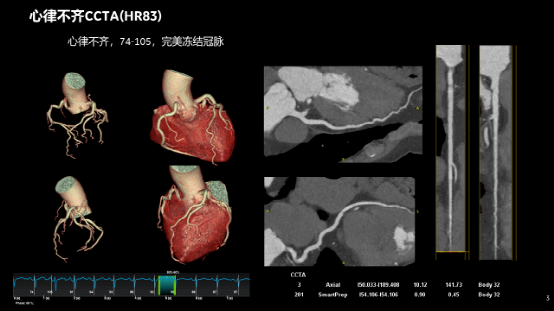

无限制1-Beat 1-Stop心脏成像

在任何心率和心律条件下,一次对比剂注射、 一个心动周期内就可以获得心脏的冠脉解剖信息、斑块成分信息